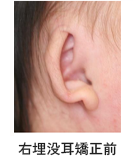

3. 耳介

妊娠の2ヵ月から3ヵ月の時に6つの膨らみが頚の位置にできて、徐々に耳の形ができてきます。標準的な耳の形は縦横の比率が2:1と縦が長く、縦の長さは成人男性では65㎜前後、成人女性では60㎜程度とされています。 しかし、耳の形や大きさは人によりさまざまで、全く同じ顔の人がいないのと同様に全く同じ形耳の人もいないと言っても過言ではありません。

乳児の耳介は可塑性があるため、歯の矯正と同様に耳介も矯正治療ができる事がはっきりしてきました。耳の矯正治療は本人が嫌がって外そうとする手の動きができるようになる前の生後3ヵ月以内が最も効果的です。

乳児の耳介は可塑性があるため、歯の矯正と同様に耳介も矯正治療ができる事がはっきりしてきました。耳の矯正治療は本人が嫌がって外そうとする手の動きができるようになる前の生後3ヵ月以内が最も効果的です。

耳変形

埋没耳変形

耳の矯正治療